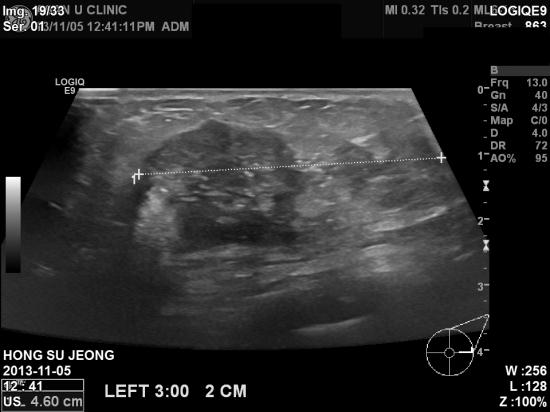

초음파검사결과 좌측유방에 4cm 가 넘는

혹이있었고

겨드랑이 임파절에도

전이소견보여 조직검사를 시행하였습니다